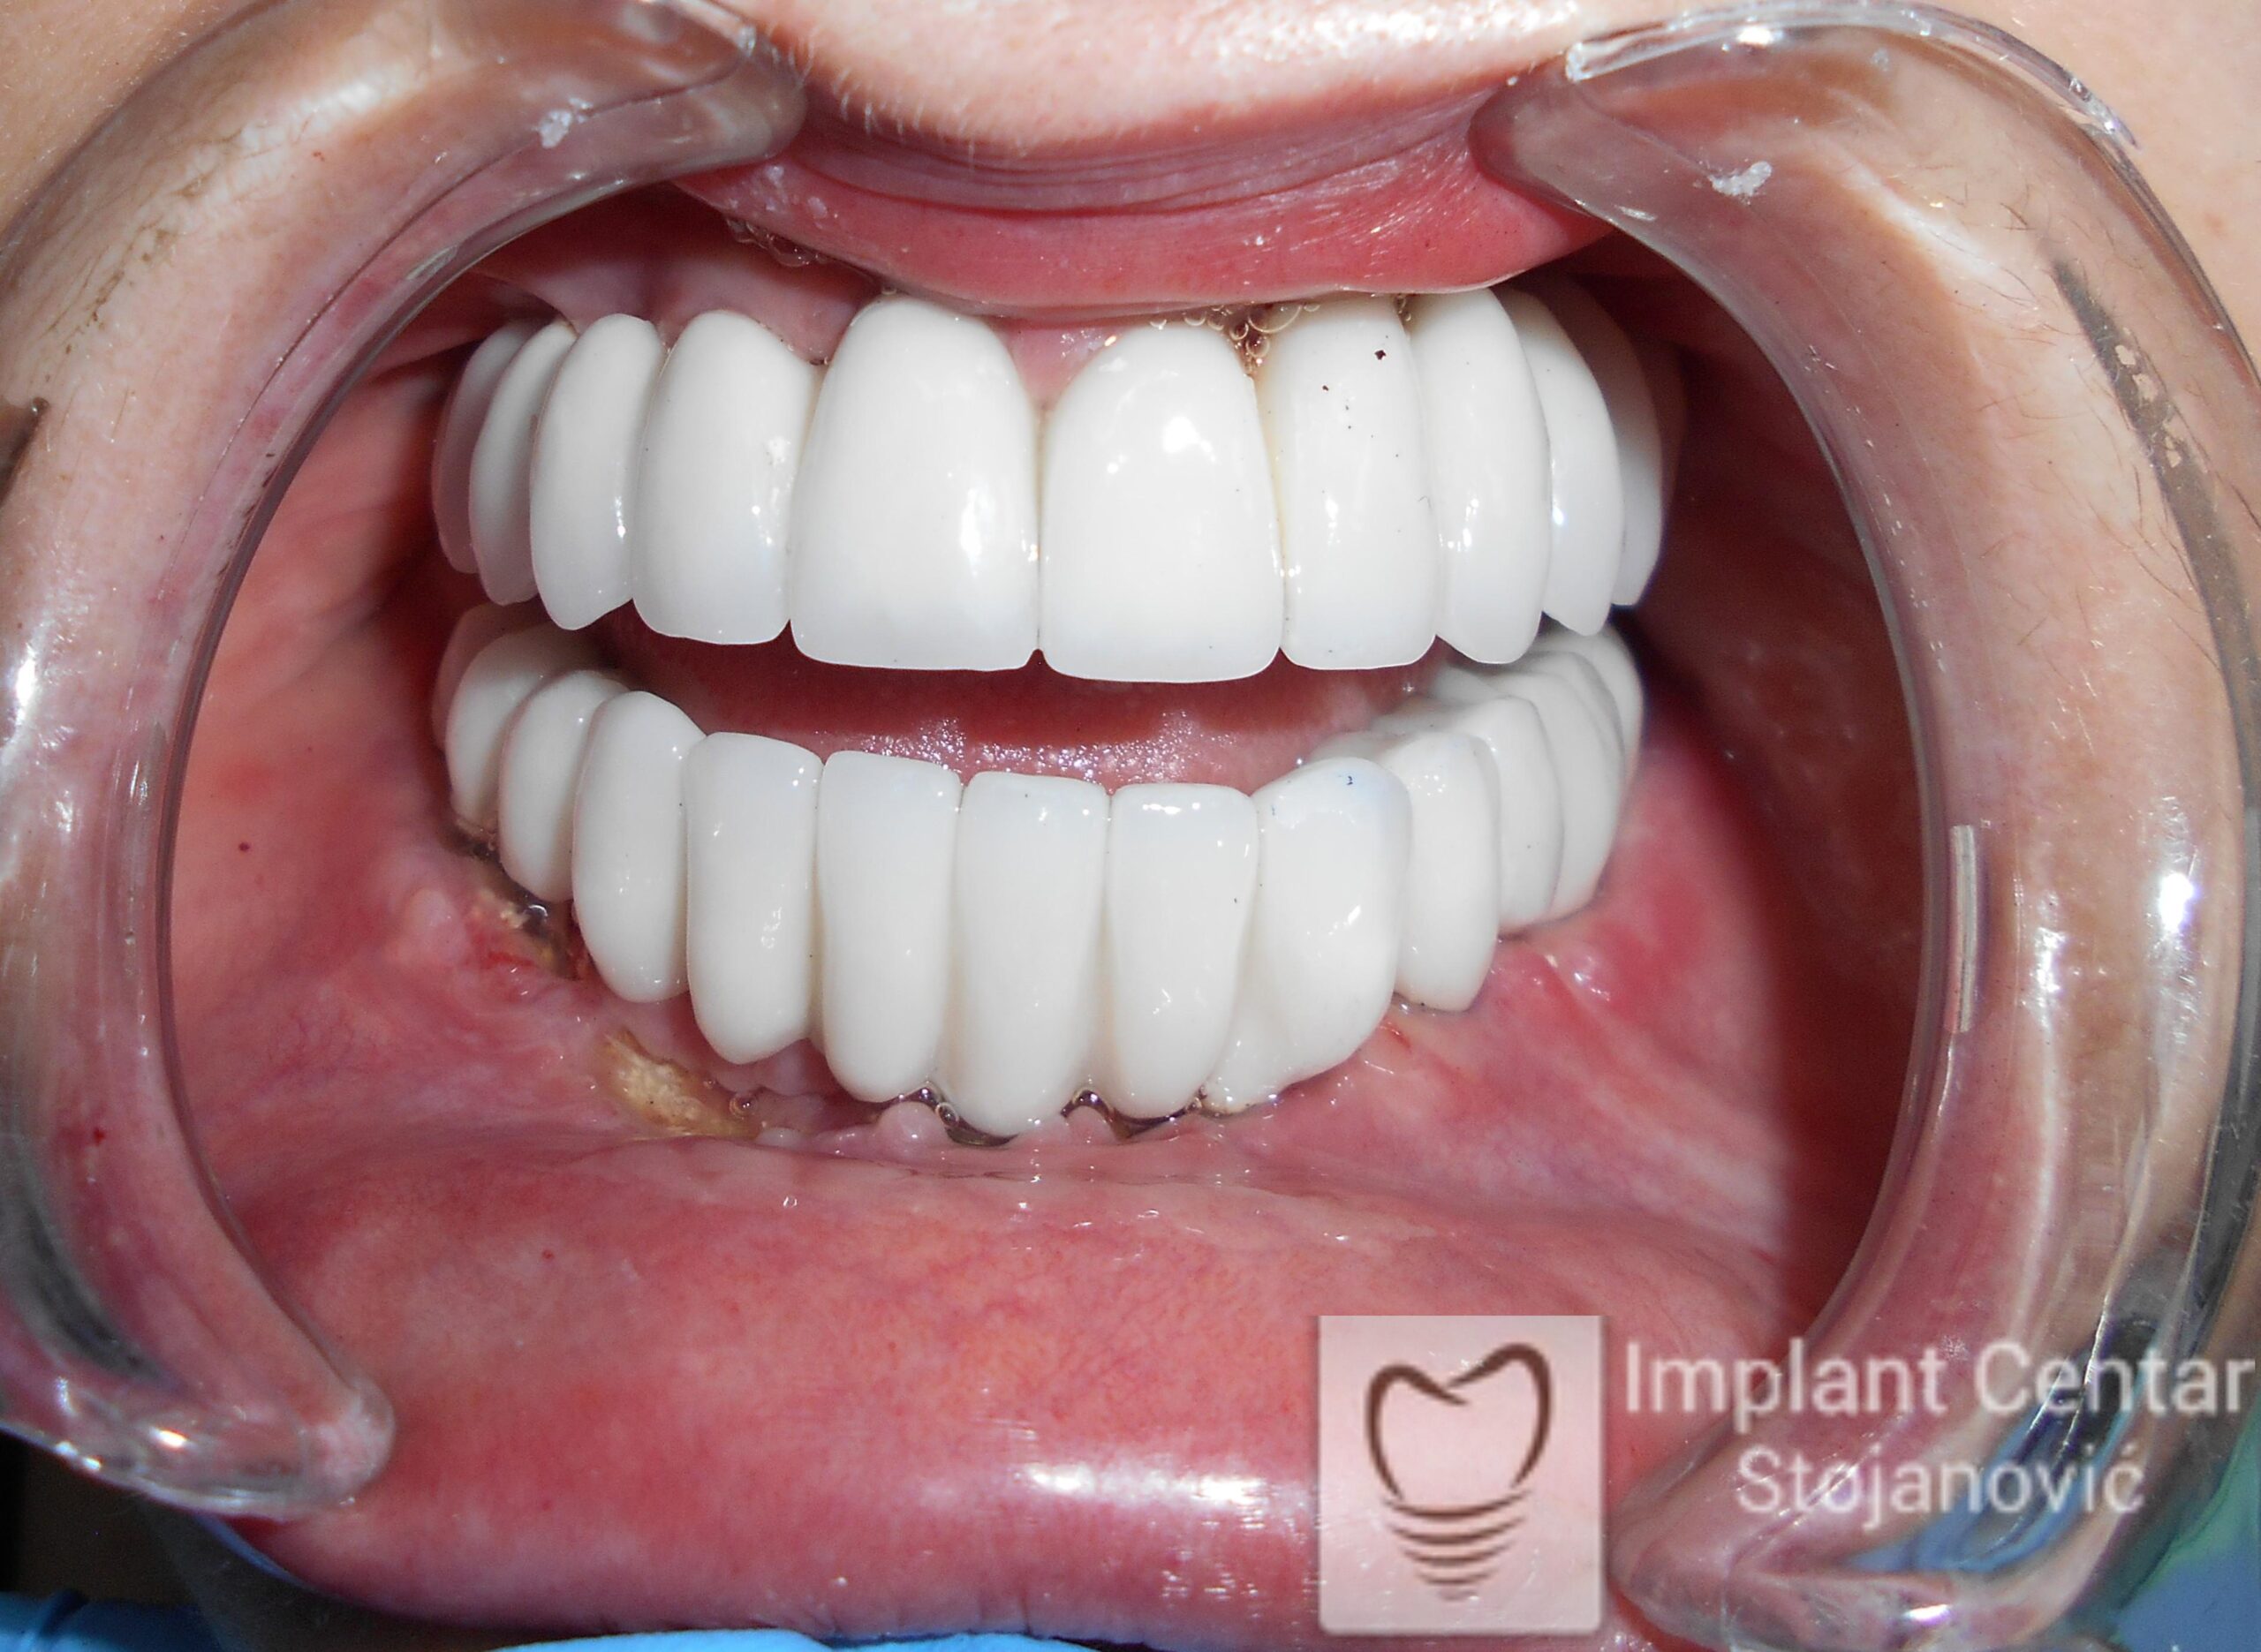

Ugrađeno je deset implantata u gornjoj vilici, u raspoloživu kost uz dodavanje veštačke kosti, od čega su dva tuberopterigoidna implantata. Ovim pristupom izbegnuta je potreba za sinus liftom, a postignuta maksimalna stabilnost.

Veći broj implantata omogućio je ravnomeran prenos žvačnih sila i izuzetnu stabilnost budućeg fiksnog rada.

U donjoj vilici su istovremeno izvađeni svi preostali zubi i ugrađeno je osam implantata.

Kompletna rehabilitacija – hirurška i protetska faza – trajala je tri meseca.

Tokom tog perioda pacijent je u gornjoj vilici nosio privremenu totalnu protezu, a u donjoj vilici imao fiksne privremene zube postavljene na tek ugrađene implantate.

Nakon završetka procesa izrađeni su fiksni cirkonijum–keramički (bezmetalni) mostovi u obe vilice.

Rad je uspešno završen pre četiri godine, a rezultati su i dalje besprekorni – stabilni implantati, savršena funkcija i prirodan izgled osmeha.